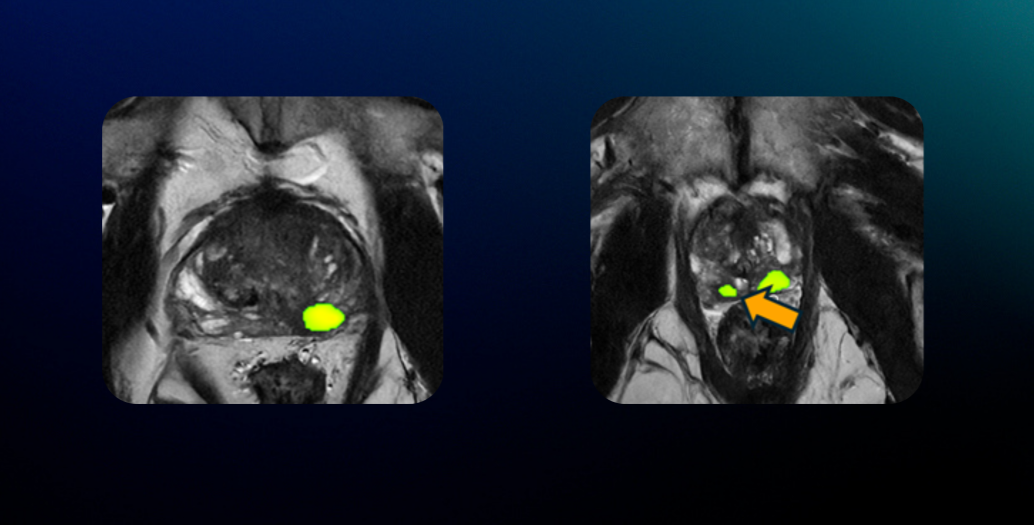

In one case, Pi™ detected a smaller lesion that had not been initially noticed. Both lesions were later confirmed by biopsy as clinically significant cancers, supporting the value of AI-assisted review in complex cases.